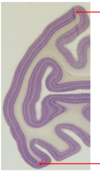

Draw the histological structure of the retina.

A